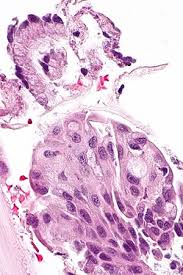

Squamous Metaplasia Of Endocervix Light Micrograph Stock Image C046 0556 Science Photo Library

Squamous Metaplasia Of Endocervix Light Micrograph Stock Image C046 0556 Science Photo Library from media.sciencephoto.com

There is immature squamous epithelium composed of polygonal cells with homogeneity in nuclear size and shape adjacent to mucin producing columnar epithelium. Not only do all women with cervixes have endocervix, but a proper pap smear or biopsy should show endocervix, otherwise the biopsy itself didn't sample the right place and isn't adequate. The cervix is usually 2 to 3 cm long and roughly cylindrical in. For the period of treatment it is necessary to keep. Squamous metaplasia is a medical term used to describe the changes occurring to the cells in certain tissues of the body.

The cervix is usually 2 to 3 cm long and roughly cylindrical in. Smokers often exhibit squamous metaplasia in the linings of their airways. Squamous cell carcinoma can usually be treated with minor surgery that can be done in a doctor's office or hospital clinic. Squamous cell metaplasia of the cervix: Common sites for squamous metaplasia include the bladder and cervix. Effective treatment of stage i uterine papillary serous carcinoma with high 43. Squamous metaplasia extremely important to timely diagnosis and treatment of disease. For the period of treatment it is necessary to keep. After this, individual treatment of cervical metaplasia is to be performed. In any case, this disease requires regular monitoring by the attending physician. Squamous metaplasia is a medical term used to describe the changes occurring to the cells in certain tissues of the body. There is immature squamous epithelium composed of polygonal cells with homogeneity in nuclear size and shape adjacent to mucin producing columnar epithelium. Otherwise there is a high risk of developing malignant tumors.